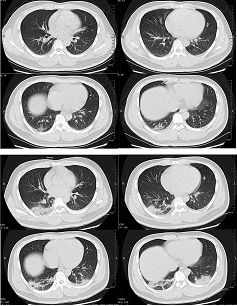

ჰოსპიტალიზებული პაციენტების 97%-მდე ნაწილს გამოუვლინდა პათოლოგიური ნიშნები გულმკერდის CT-ზე.[546] ყველაზე ხშირი გამოვლინებებია დამსხვრეული მინის სურათი, იზოლირებულად ან სხვა ნიშნებთან ერთად, როგორიცაა კონსოლიდაცია, წილაკთაშორისი ძგიდის გასქელება ან ნაკვალევის მსგავსი ნიშანი. ყველაზე ხშირი მიმდინარეობა არის ორმხრივი, პერიფერიული/პლევრის ქვეშა, უკანა წილების დაჩრდილვა, ქვედა წილების დომინანტობით. ექსტენსიური/მულტიწილოვანი ჩართულობა კონსოლიდაციით უფრო ხშირია ხანდაზმულ პაციენტებში და მძიმე დაავადების მქონე პირებში. ატიპიური ნიშნებია ფილტვის სისხლძარღვების გადიდება, მიმდებარე პლევრის გასქელება, ჰაეროვანი ბრონქოგრამები, სუბპლევრალური ხაზები, ბრონქების კონტურის ცვლილება, ბრონქოექტაზია, ვაკუოლური რეტრაქციის ნიშანი და ჰალო ნიშანი. იშვიათ შემთხვევებში ფიქსირდება პლევრული გამონაჟონი, პერიკარდიუმის გამონაჟონი, კავიტაცია, პნევმოთორაქსი და შუასაყრის ლიმფადენოპათია.[547] COVID-19-ით გამოწვეული პნევმონიის დიაგნოზს ყველაზე უკეთ ასახავს მინის ნამსხვრევისებრი დაჩრდილვები, რასაც მოჰყვება მინის ნამსხვრევისებრი დაჩრდილვები კონსოლიდაციით და მხოლოდ კონსოლიდაცია.[548]

გულმკერდის კომპიუტერულ-ტომოგრაფიული სკანირებით, როგორც წესი, ვლინდება მინის ნამსხვრევისებრი დაჩრილვების ზომის, რაოდენობრივი და სიმკვრივის ზრდა ადრეული მონიტორინგის პერიოდში. შემდგომ ვითარდება შერეული სურათი, რომელიც მოიცავს მინის ნამსხვრევისებრ დაჩრდილვებს, კონსოლიდაციებს და არეული ქვაფენილის განლაგებას, რაც პიკს აღწევს მე-10-მე-11 დღეს, შემდგომ კი თანდათანობით ლაგდება ან რჩება ლაქოვანი ფიბროზის ფორმით.[547]

[Figure caption and citation for the preceding image starts]: 32 წლის მამაკაცის კომპიუტერული ტომოგრაფია განივი ჭრილში; ვლინდება მქრქალი მინისებრი დაჩრდილვა და მარჯვენა ფილტვის ქვედა წილის კონსოლიდაცია პლევრასთან ახლოს. სურათი მიღებულია სიმპტომების გამოვლენიდან 1-ლ დღეს (ზედა პანელი); ორმხრივი მქრქალი მინისებრი დაჩრდილვა და კონსოლიდაცია ვლინდება სიმპტომების გამოვლენიდან მე-7 დღესXu XW et al. BMJ. 2020;368:m606 [Citation ends].